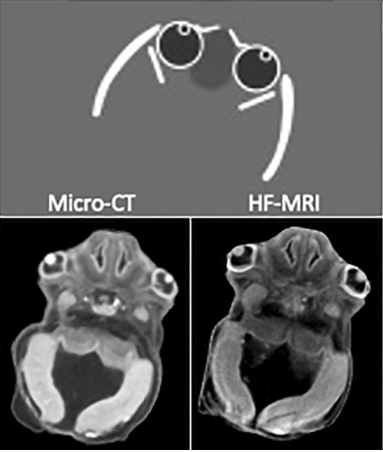

Micro-imagerie 3D à très haute définition de la tête d’un embryon à 8 mois de gestation

Le premier sujet concerne le projet FETTAL (Fetal Enhanced Tridimensional and Translational Anatomical Landscape) qui a comme objectif de développer une micro-imagerie 3D multimodale (micro-CT, nano-IRM, tissulaire et transcriptomique) prénatale à des stades précoces de développement, notamment à la transition de l’embryon au fœtus. L’intérêt pour le développement de structures complexes comme la face est majeur dans la compréhension des malformations de la tête et du cou. L'utilisation de la micro-imagerie, comme moyen d’exploration non invasive, permettra une meilleure caractérisation des malformations et une aide pour le diagnostic de précision. Une thèse sur le protocole de micro-imagerie chez le fœtus de 12 SA est en cours.